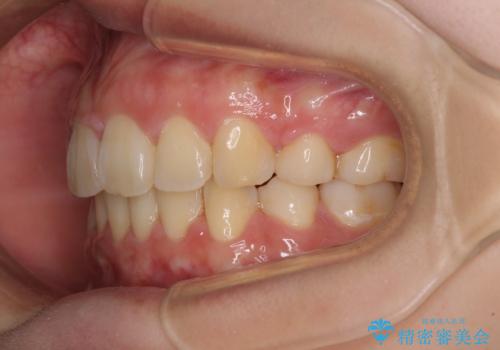

治療後には口が閉じやすくなり、患者様には大変満足していただきました。